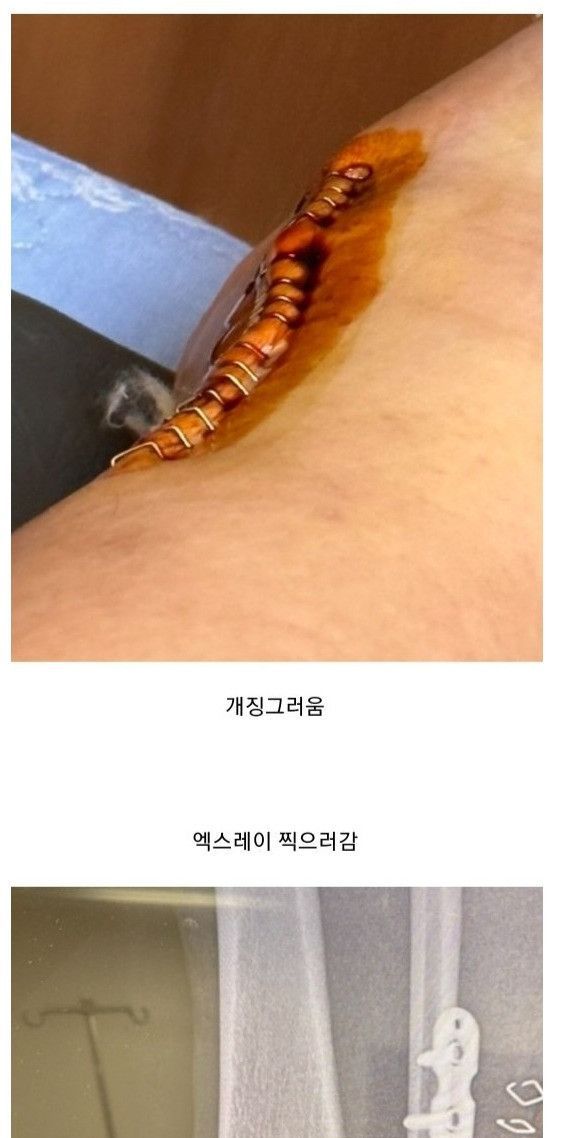

빙판길에서 자빠져 발목 부러져서 수술

수술했는데 하나도 안아픔